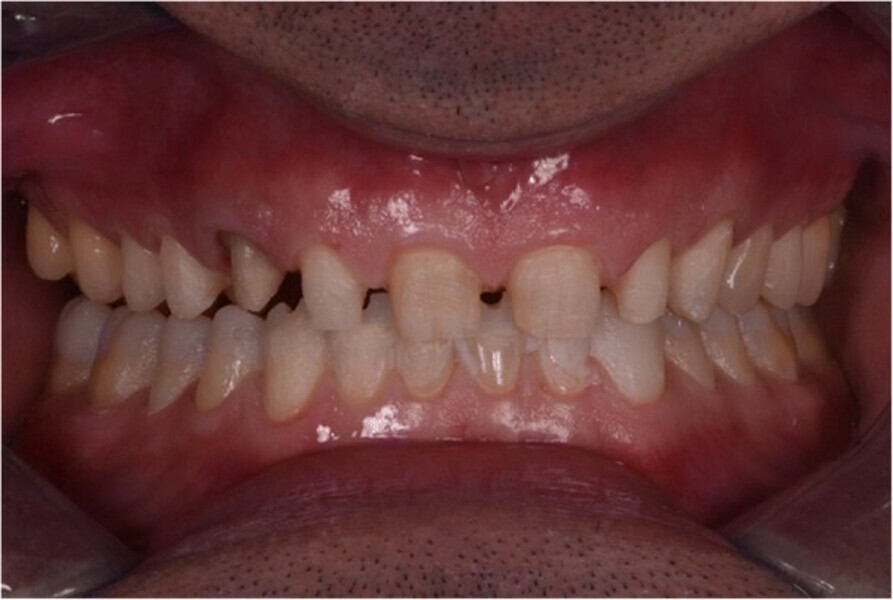

Fig. 1. Fotografías intraorales iniciales, vista frontal (A), vista oclusal del maxilar (B) y vista oclusal de la mandíbula (C).